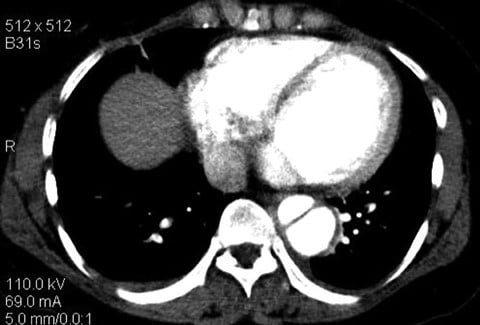

Aortic dissections can be classified using 2 systems: Stanford and DeBakey. The Stanford classification system categorizes dissections according to whether they require surgical repair (type A) or can be managed using medications to control blood pressure (type B).1 Type A dissections affect the ascending aorta, whereas type B dissections do not (see Figures 1 and 2).2 The DeBakey system also categorizes dissections by required medical intervention; however, this classification system details the process, or origination, of the dissection and is divided into types I, II, and III. Type I dissections originate in the ascending aorta, likely continue through the aortic arch, and often involve the descending aorta or even the entire aorta.2 Type II dissections affect only the ascending aorta, while type III dissections solely affect the descending aorta (see Box ).2 The most common aortic dissections occur in the descending aorta.3